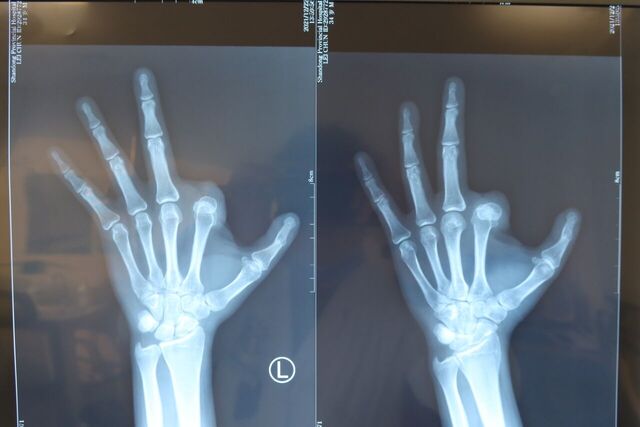

示指长手指再造。术后1年随访

微信图片_20230921213851.jpg 微信图片_20230921213905.jpg 微信图片_20230921213916.jpg 微信图片_20230921214427.jpg 微信图片_20230909224030.jpg 微信图片_20230909224014.jpg 微信图片_20230909224025.jpg 微信图片_20230909224007.jpg 微信图片_20230909224002.jpg 微信图片_20230909223945.jpg 微信图片_20230909224010.jpg 微信图片_20230909224018.jpg